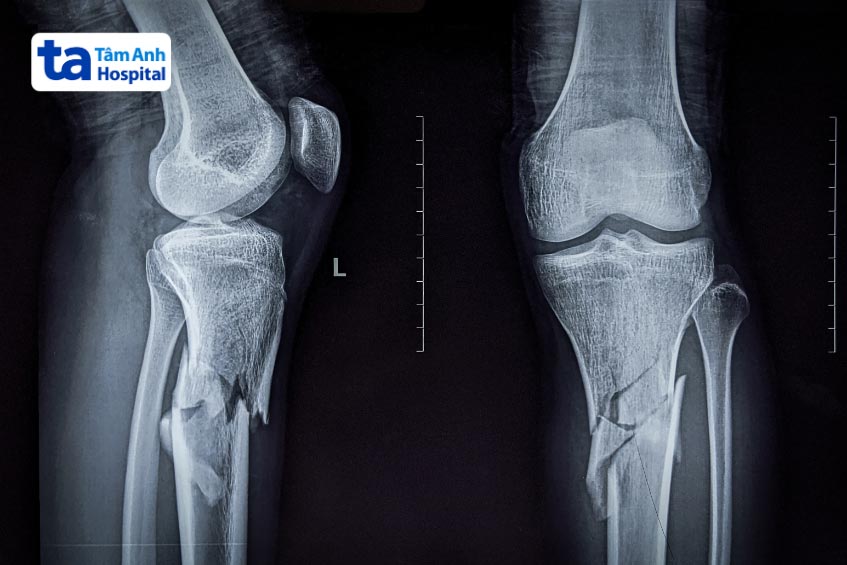

Viêm khớp gối có nguy hiểm không? Tình trạng viêm khớp gối tiến triển có thể gây hư sụn khớp gối. Khi sụn bị mòn đi, xương dưới sụn sẽ dày lên và cứng lại, đồng thời các gai xương có thể hình thành ở các cạnh của xương. Những thay đổi này sẽ hạn chế phạm vi chuyển động của khớp, đồng thời kích thích gân và dây chằng, gây đau đớn cho người bệnh. Trường hợp nghiêm trọng, một số phần của sụn có thể bị mất hoàn toàn, dẫn đến việc các xương trong khớp cọ xát trực tiếp vào nhau, gây đau khi đi lại. Viêm khớp gối lâu ngày cũng dẫn đến tổn thương dây chằng bên trong khớp gối.

Viêm khớp gối kéo dài có thể làm tăng nguy cơ loãng xương. Các nghiên cứu chỉ ra rằng mật độ khoáng xương ở những người mắc viêm khớp gối nặng thường thấp hơn so với người bình thường. Một trong những biến chứng nghiêm trọng nhất của loãng xương chính là gãy xương. Do tình trạng này làm suy giảm độ bền của xương, từ đó làm tăng nguy cơ gãy xương, đặc biệt ở khu vực khớp gối.

Nhiều trường hợp người bệnh bị viêm khớp gối nhưng lại chủ quan không điều trị khiến bệnh chuyển biến ngày càng nặng, dẫn đến thoái hóa khớp gối không thể chữa. Thoái hóa khớp gối hay còn gọi là thoái hóa sụn khớp gối, là tình trạng lớp đệm giữa các khớp bị mài mòn. Khi lớp đệm này bị mất, xương giữa các khớp sẽ cọ xát mạnh với nhau. Không còn sự bảo vệ từ sụn, người bệnh sẽ cảm nhận được cơn đau, sưng, cứng khớp, thậm chí làm giảm khả năng di chuyển.

Viêm khớp gối có nguy hiểm không? Khi tình trạng viêm khớp gối tiến triển, tổn thương sụn khớp theo thời gian có thể dẫn đến biến dạng đầu gối. Khi những biến dạng này trở nên trầm trọng hơn sẽ gây biến đổi trục chi như đầu gối cong và chân vòng kiềng. Điều này không chỉ gây khó khăn trong việc vận động mà còn ảnh hưởng nghiêm trọng đến thẩm mỹ và chất lượng cuộc sống của người bệnh. (3)